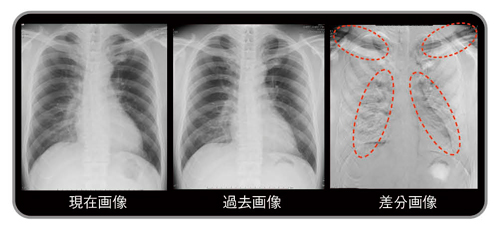

図1 差分画像の見え方

1980年代に商品化されたデジタル画像は,その後急速に普及し,2010年代の今ではほとんどの医療用画像はデジタル化され,モニタにより診断や治療が行われている1)。本稿で紹介する経時的差分法(temporal subtraction:TS)は,現在画像から過去画像を自動的に引き算して,変化のあった病変のみを強調して表示する手法で,新しく出現した病変を黒く表示し,消失した病変は白く表示させることで読影を支援するシステムである(図1)。

左上肺野の小結節出現(黒く表示),右中肺野の肺炎消失(白く表示)

従来の比較読影に,さらに差分画像を追加することにより,正常肺構造や既存肺病変に隠れがちな新規病変は,病変のみが明瞭に描出されるようになるため,読影時の気づきに大きな貢献が期待できる。また,従来の読影法のように一か所ごとに病変を見比べるのではなく,差分画像を一瞥するだけで胸部全体の変化のある病変だけを把握でき,読影時間の短縮につながることが期待できる。